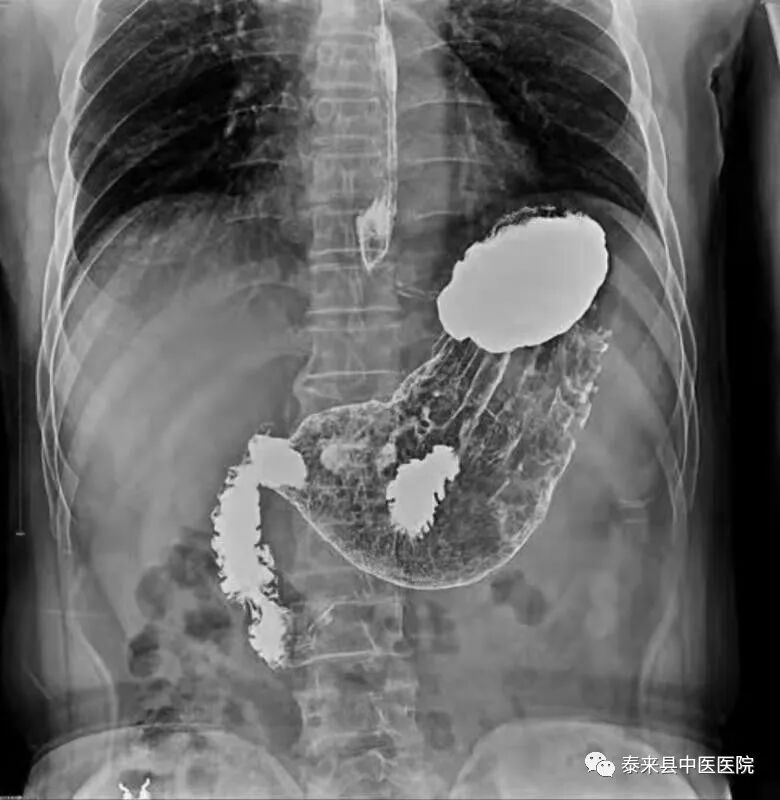

数字化胃肠透视检查以其痛苦微小、快捷安全的优点,对功能性、器质性病变(吞咽功能障碍,贲门失弛缓症,胃下垂,粘膜脱垂等)进行动态实时观察、整体与局部相结合的方法,有效的减少了内镜及CT、MR检查盲区,对术后复查及常规筛查的患者提供了更多的诊断依据。

2、数字化造影

将密度和组织器官有差异的造影剂导入人体检查部位,并检查组织器官是否存在病变。通过动态摄影观察组织器官的功能运行情况,并实时点片摄影。适用于食管、上消化道、全消化道等普通造影及静脉胆道造影、T管造影、静脉肾盂造影、逆行肾盂造影、子宮输卵管造影、膀胱造影、脊髓造影等普通及特殊造影。